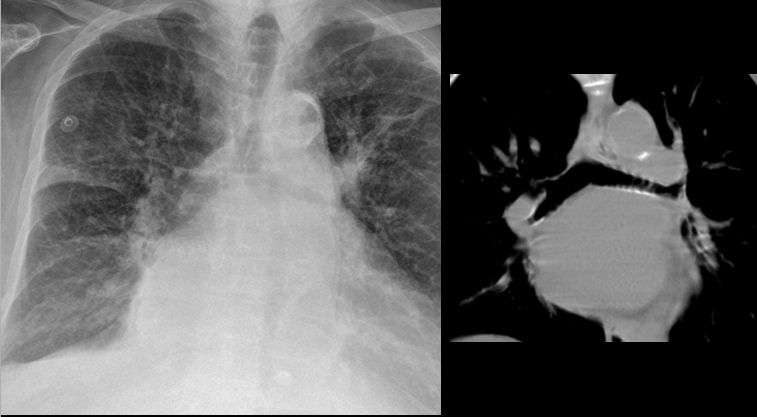

Gallery Cardiac Mitral Valve Disease Enlarged Lt atrium, splaying

Enlarged Lt atrium, splaying